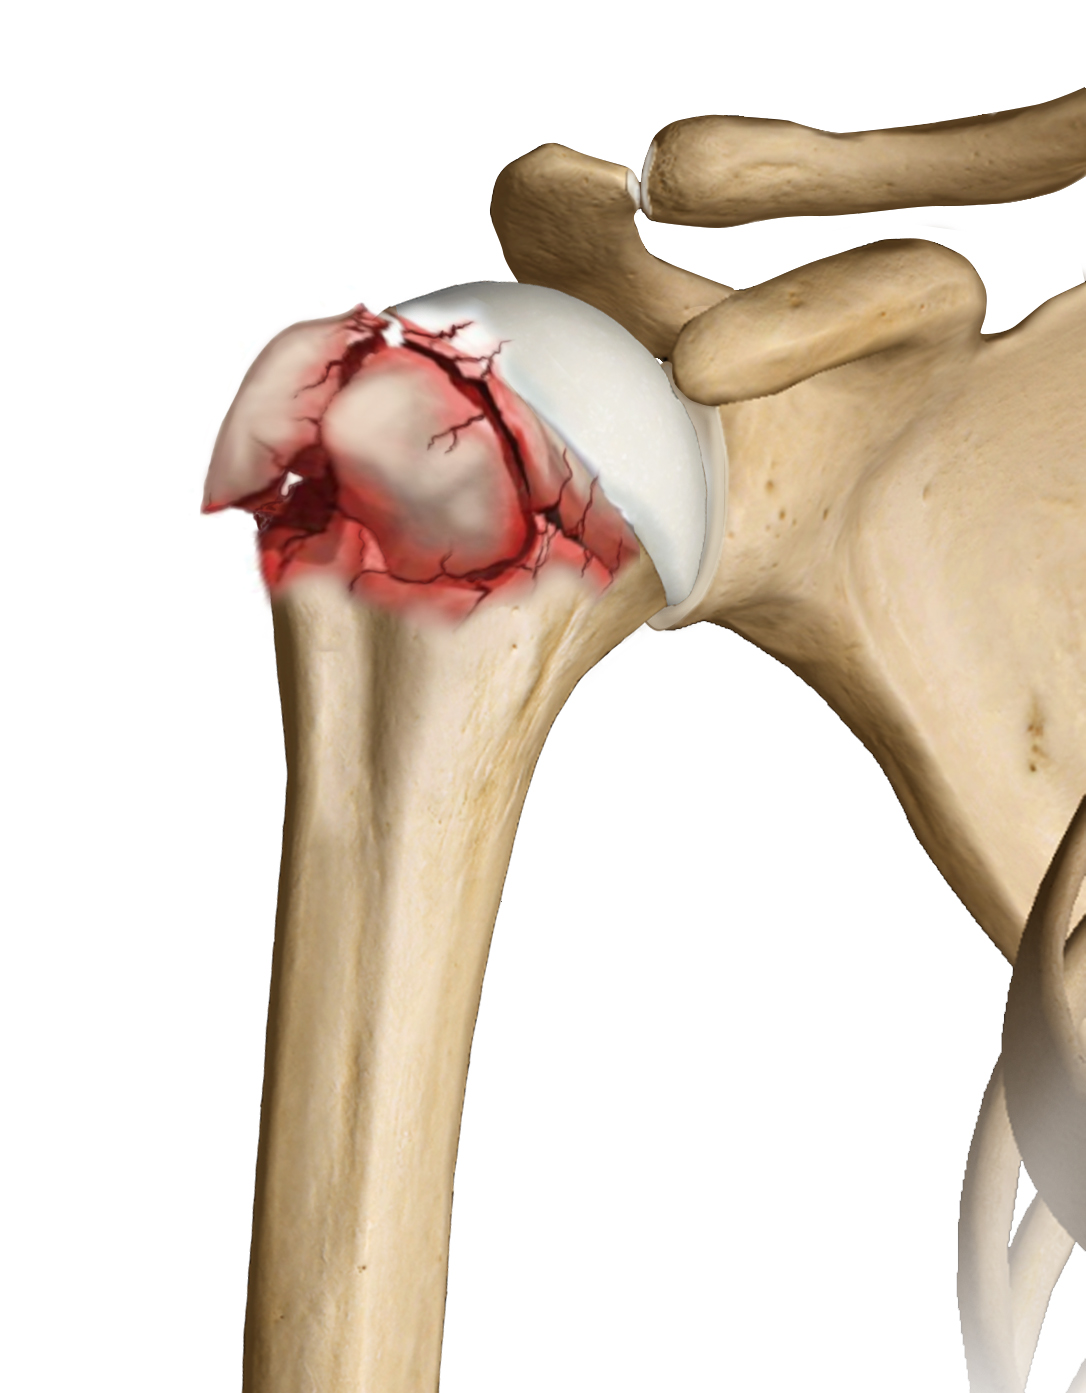

L'artrite reumatoide è la forma più comune di un gruppo di disturbi denominato "artriti infiammatorie". - Artrite post-traumatica: Forma di artrite conseguente ad un grave infortunio alla spalla. Le fratture osse o le lesioni tendinee e legamentose possono portare ad un rapido deterioramento della cartilagine articolare causando dolore e limitazione funzionale.

- Necrosi vascolare: La necrosi avascolare è una condizione dolorosa che si verifica quando l’apporto sanguigno all'osso viene interrotto cosi causando la morte delle cellule costituenti l’osso. Possibili cause che portano allo sviluppo di questa condizione sono: l'uso cronico di steroidi, la frattura grave della spalla, malattie ematologiche e l'abuso di alcol.

- Gravi fratture: Fratture trattate in modo scorretto possono portare a una progressiva deformazione dell’articolazione stessa.